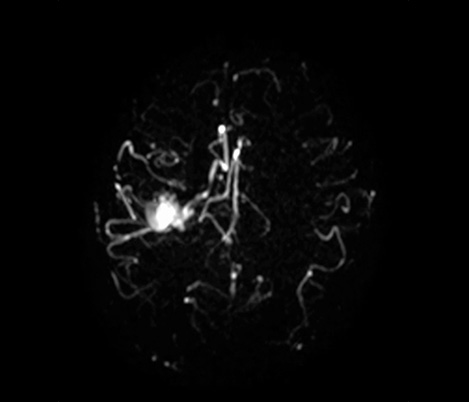

Da colaboração O Dr. Tetsuya Yoneda, Universidade de Kumamoto, Japão, fala sobre a sua colaboração com a Philips numa técnica denominada SWIp desenvolvida para a imagiologia com suscetibilidade ponderada.

...à prática clínica O Dr. Chip Truwit, Hennepin County Medical Center, Minneapolis, EUA, explica como o SWIp se tornou parte integrante de todos as exames de lesões de RM.